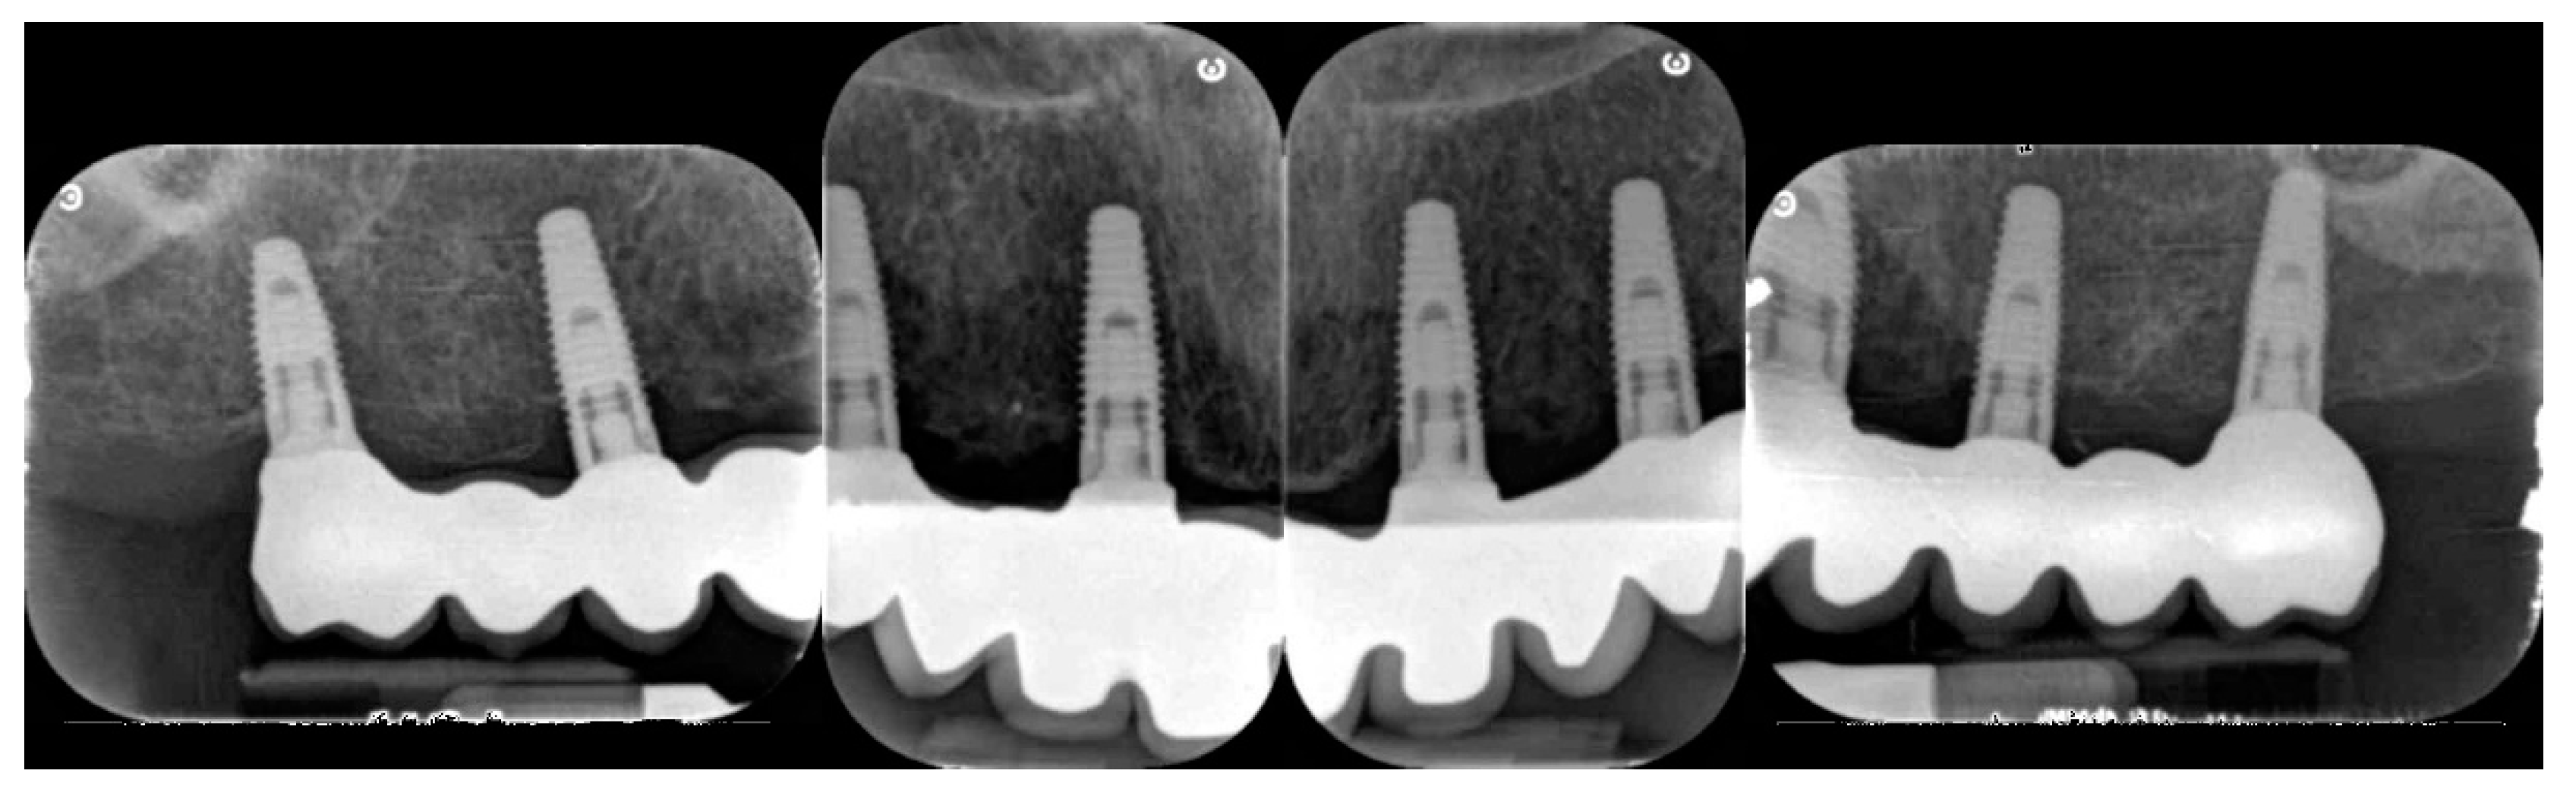

- Peri-implant bone levels changes were measured as the distance between mesial and distal margin of the implant neck (inserted slightly below buccal bone level) to the most coronal point where the bone looked to be in contact with implant. Mean values of mesial and distal measurements were calculated for each implant. Measurements on digital periapical radiographic images, obtained by parallel cone technique with extension cone paralleling instrument (Rinn XCP, Dentsply, Elgin, IL, USA), were taken after implant placement (baseline) and three years after final loading. All radiographs have been analyzed through a software (DFW2.8 for Windows, Soredex, Tuuka, Finland), calibrated for each image using the known distance between two implant threads’ consecutive steps. In case of an unclear image, the radiograph was taken again. A dentist, not previously involved in this study, performed every radiographic measurement.